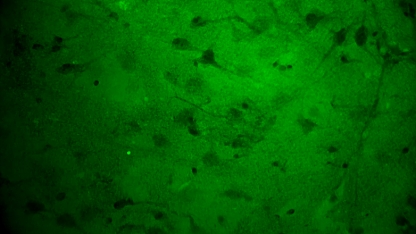

关颅期间,专家团队将其余3块瘤体组织应用EndoSCell®扫查以观察肿瘤细胞形态,无一例外,3块组织的细胞图像均符合“核异型性明显、分布密集且不规则”的肿瘤形态特征,其中一块还意外发现了清晰的神经元细胞。EndoSCell®高清直观的细胞图像给专家们留下了深刻印象,参与本次手术的张帅专家表示有合适机会或将尝试在体应用。

3.神经元细胞:神经纤维束清晰、密度低。